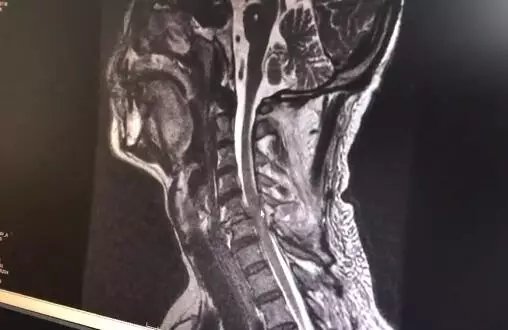

「我還從來沒有見過因為被狗砸倒造成這樣的傷情。」郴州市第一人民醫院脊柱外科醫生童傑博士介紹,哈士奇砸中了主人的頸後部,導致當事人劉先生頸椎骨折脫位脊髓損傷。

目前傷者已經進行了相關檢查,後續將進行手術治療,預計手上精細力量恢復需要3個月至半年。